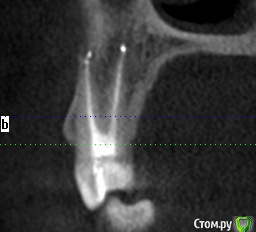

Прикрепляю не очень удачные скриншоты из КТ, которая была сделана через 4 дня после пломбировки каналов. К сожалению, других снимков на руках нет, только КТ.

post-58215-0-93459700-1563461560_thumb.jpg